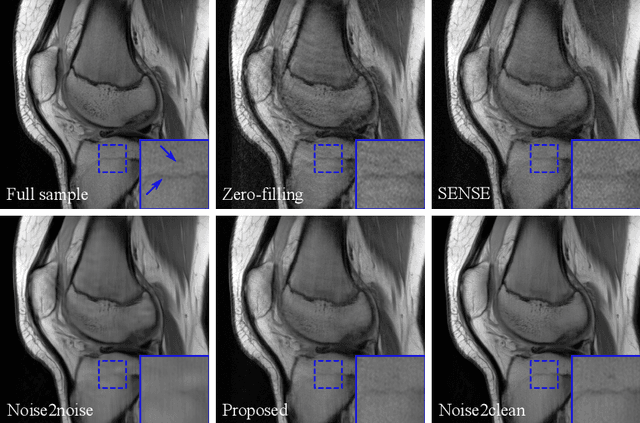

Deep neural networks have been proved efficient for medical image denoising. Current training methods require both noisy and clean images. However, clean images cannot be acquired for many practical medical applications due to naturally noisy signal, such as dynamic imaging, spectral computed tomography, arterial spin labeling magnetic resonance imaging, etc. In this paper we proposed a training method which learned denoising neural networks from noisy training samples only. Training data in the acquisition domain was split to two subsets and the network was trained to map one noisy set to the other. A consensus loss function was further proposed to efficiently combine the outputs from both subsets. A mathematical proof was provided that the proposed training scheme was equivalent to training with noisy and clean samples when the noise in the two subsets was uncorrelated and zero-mean. The method was validated on Low-dose CT Challenge dataset and NYU MRI dataset and achieved improved performance compared to existing unsupervised methods.